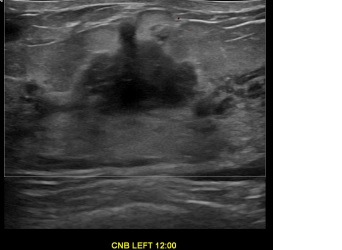

상기환자는 좌측유방통증과 만져지는 멍울있어  내원하신 40대초반

여성분으로 의심스러운 좌측혹 조직검사 시행해 유방암 진단되었습니다.